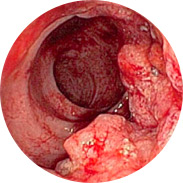

Vnetje in suppuracija rektalne sluznice

Krvavitev lahko vodi do razvoja anemije

Povišanje telesne temperature pri hudem vnetju lahko povzroči

mrzlico

In najhuje je rak danke!Obsežna klinična študija Hemorena je bila izvedena v Kliničnem centru (Ljubljana) leta 2016. Skupaj je v študiji sodelovalo več kot 1000 moških in žensk z različnimi stopnjami hemoroidov. Vsi preiskovanci so 3 tedne uporabljali kremo Hemoren. Rezultati študije so osupnili celo zdravnike!